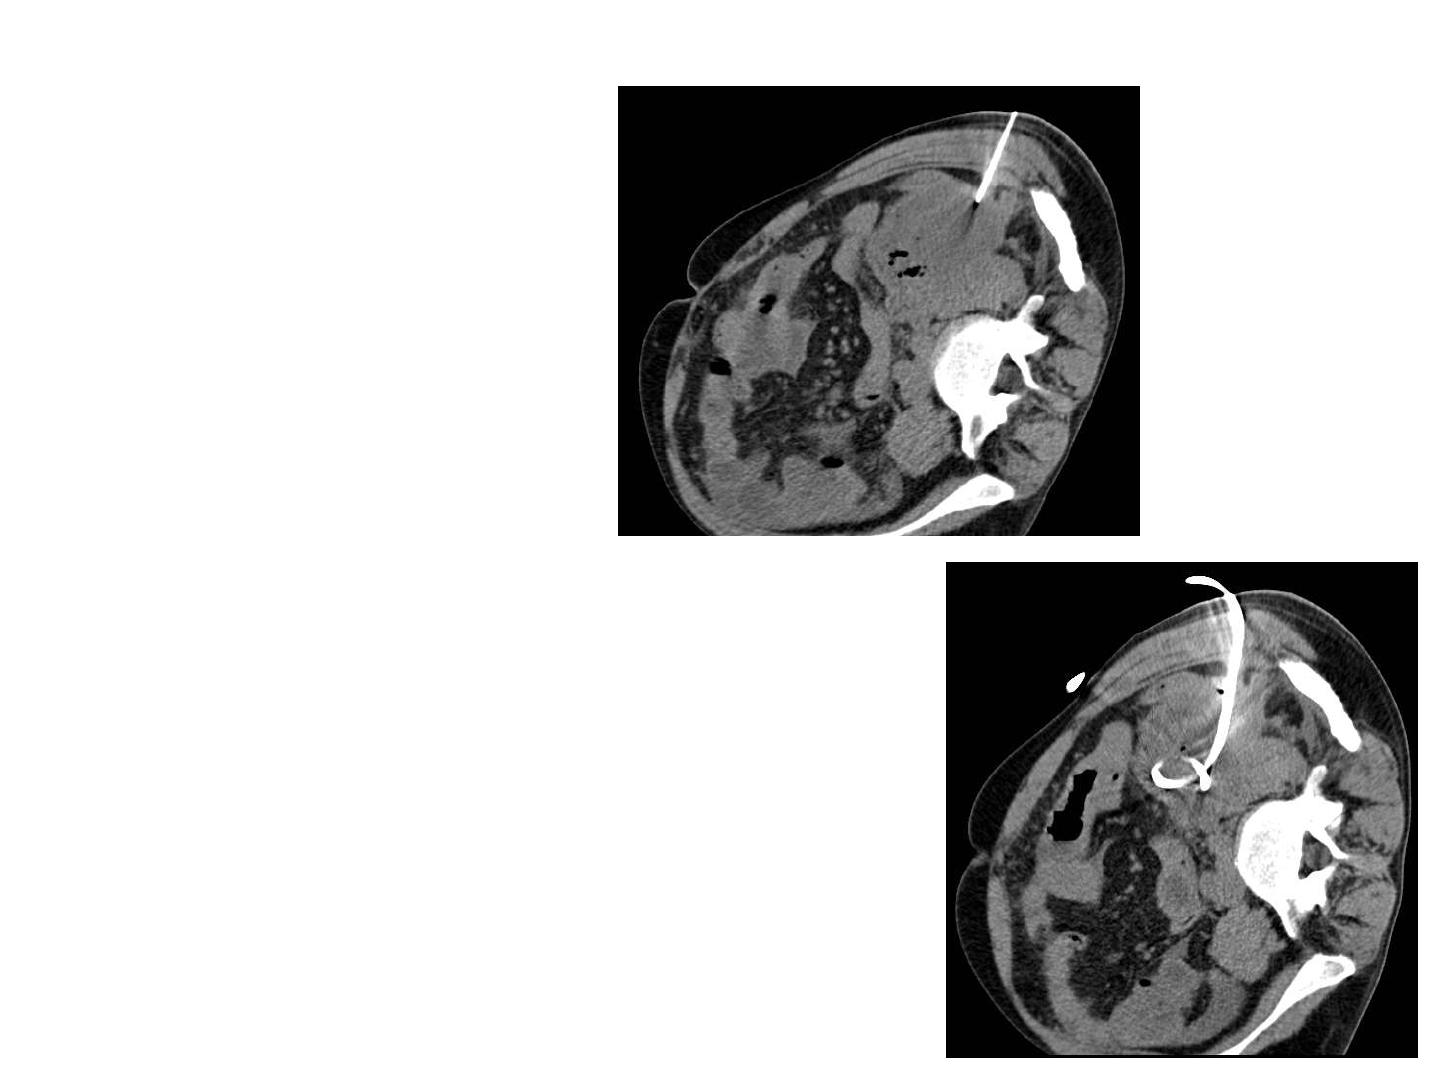

Exemple de cas

difficiles

Pancréatite aigüe

grave crosante

et surinfectée

Demande de

drainage

radiologique

Drainage « au plus simple »

Plan axial, drain 14 F